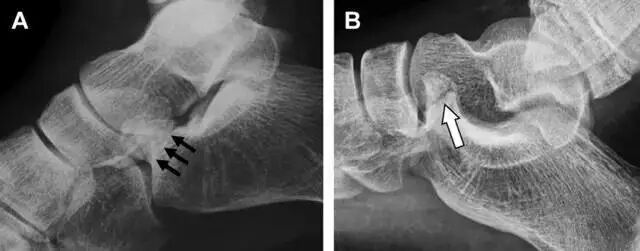

距骨后突有内侧结节和外侧结节,距骨后突内侧结节撕脱性骨折常发生在背屈内旋的暴力作用下。严重跖屈时,胫骨后缘和跟骨挤压距骨后突外侧结节呈楔形,易发生粉碎性骨折。这些骨折细微且需与三角骨鉴别。侧位片观察距骨后突骨折最佳,常规拍片很难发现,当高度怀疑这种骨折又没法做 CT 时,建议加做多个角度的外旋斜位片(图 5)。

图 5 距骨后突骨折。侧位片(A)和 MRI 矢状位 T1 加权像(B)均示后外侧突的简单骨折(箭头),再次阅片时才发现 X 线片上的骨折;侧位片(C)和 CT 横断面图像示后内侧突的粉碎型骨折(箭头)